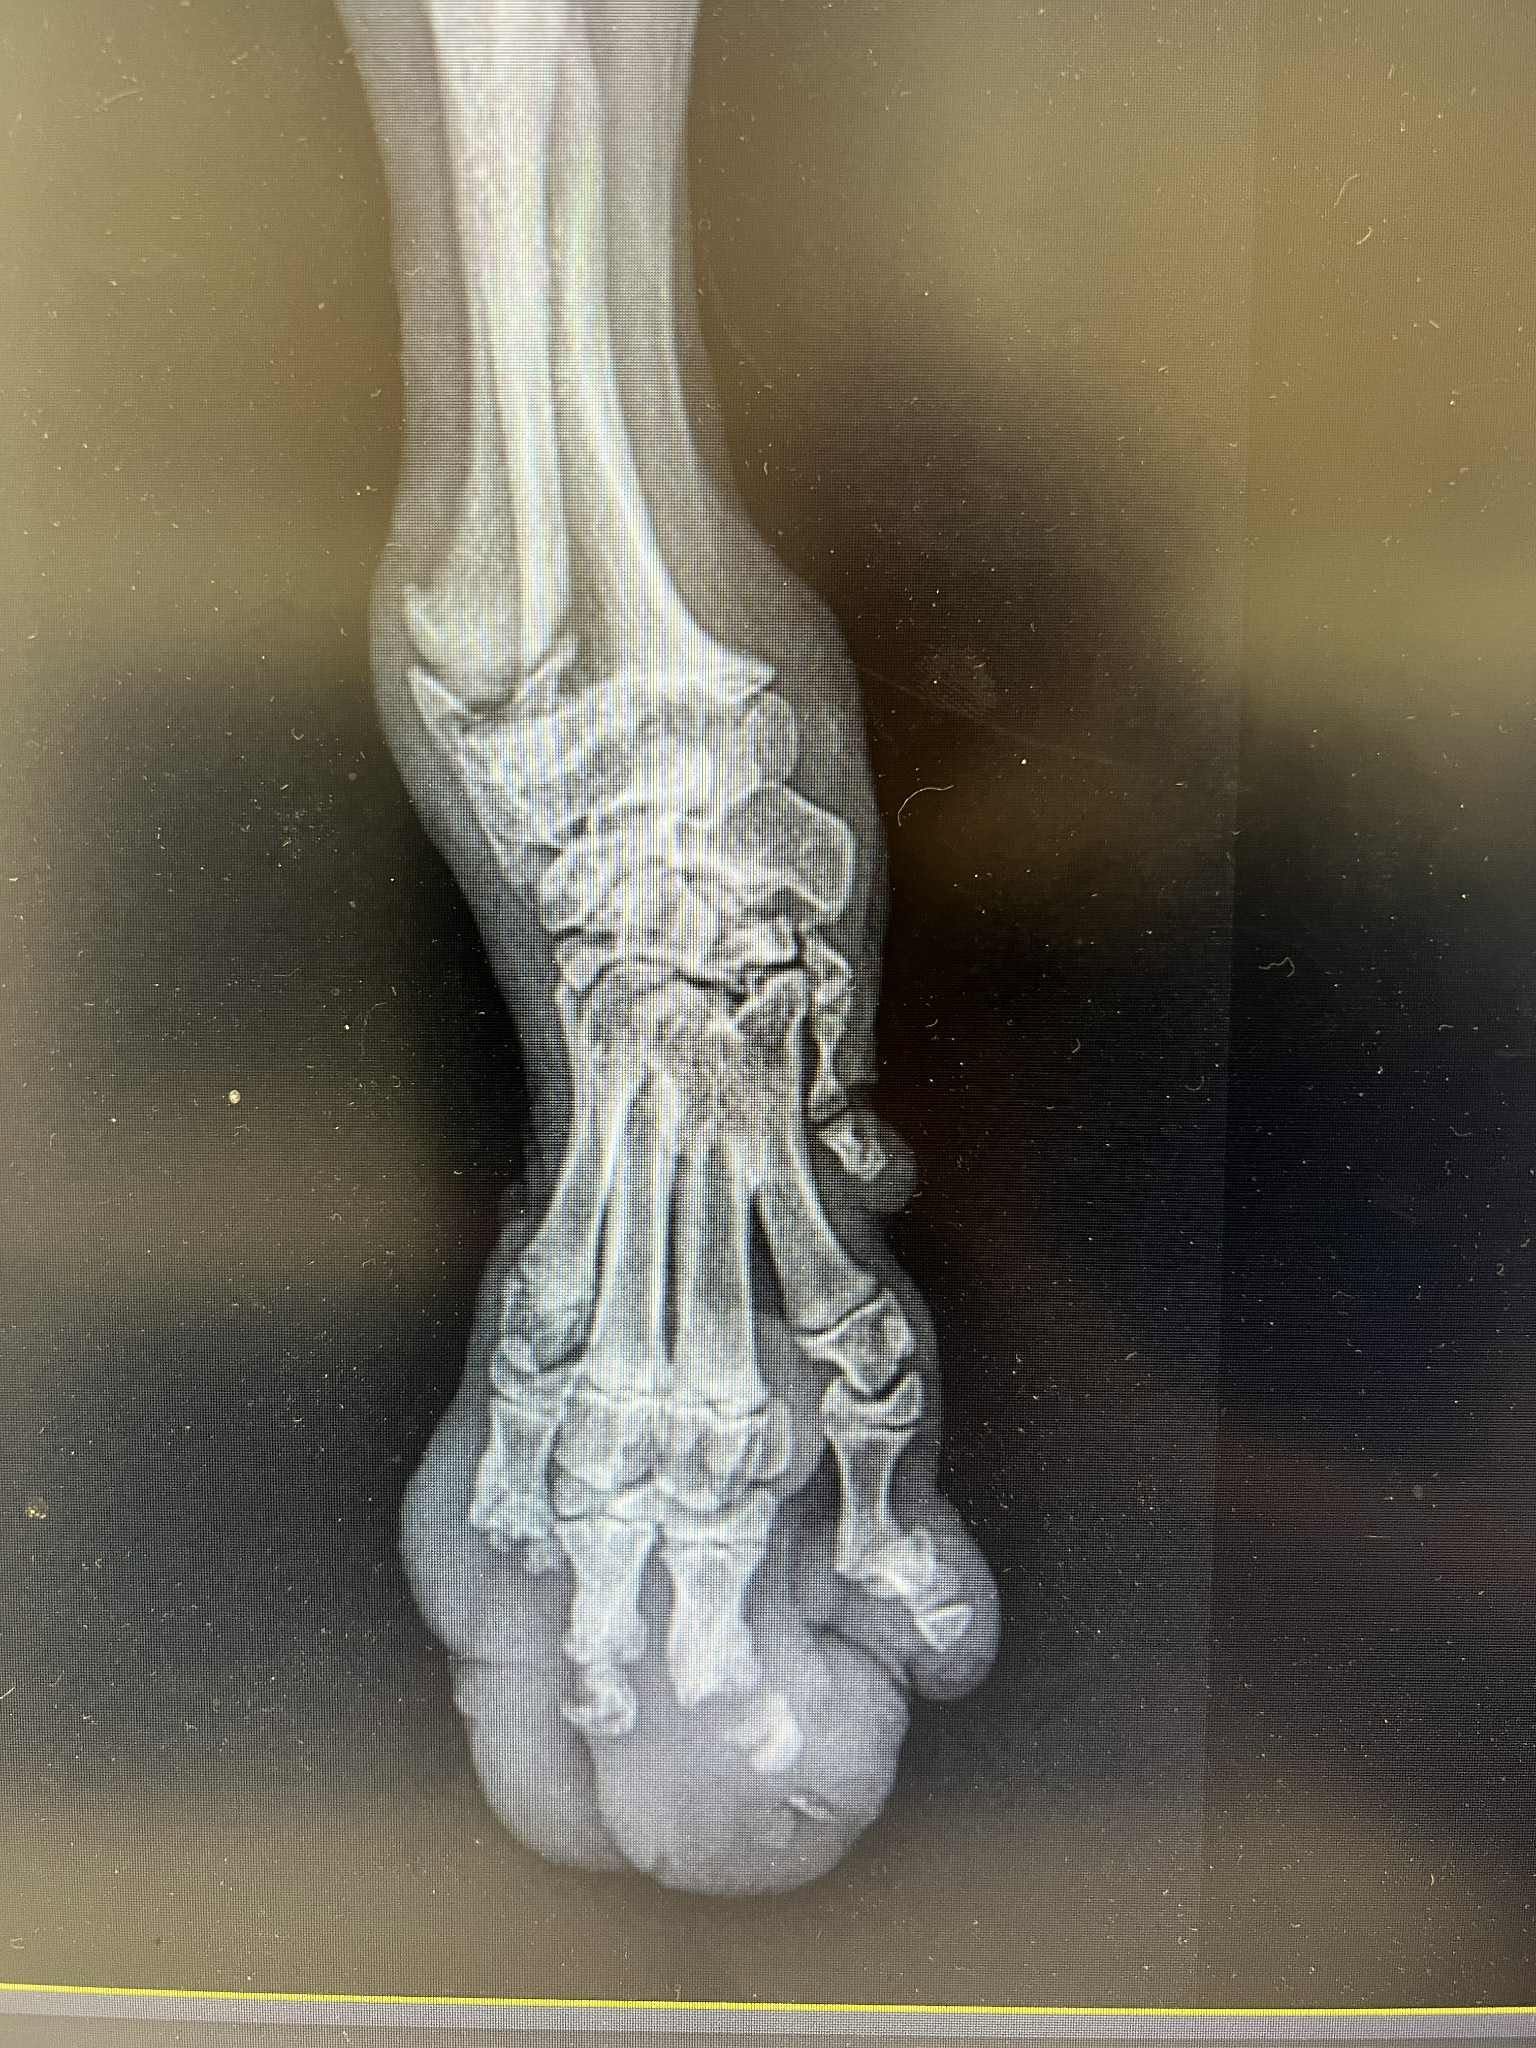

Atvyko su sužeista koja kaip ir keli kiti broliai sesės – deja nežinome nei kas nei kaip nuskriaudė mažylius.. Laukas beveik nevaikščiojo keturiomis, tad visai neliūdi – trimis kojomis ir prieš operaciją šuoliavo greičiau už kitus.

Apie 6mėn, trikojis berniukas.

Veterinarai dar stebi Lauko vystymąsi ir mano, jog netolimoje ateityje gali prireikti protezo priekinei kūno daliai, kad vienai likusiai kojai netektų didelis krūvis, nediltų sąnariukai. Nors fizinių apribojimų šiuo metu nėra, naudinga būtų pastiprinti raumenyną, neskatinti perteklinio šokinėjimo.